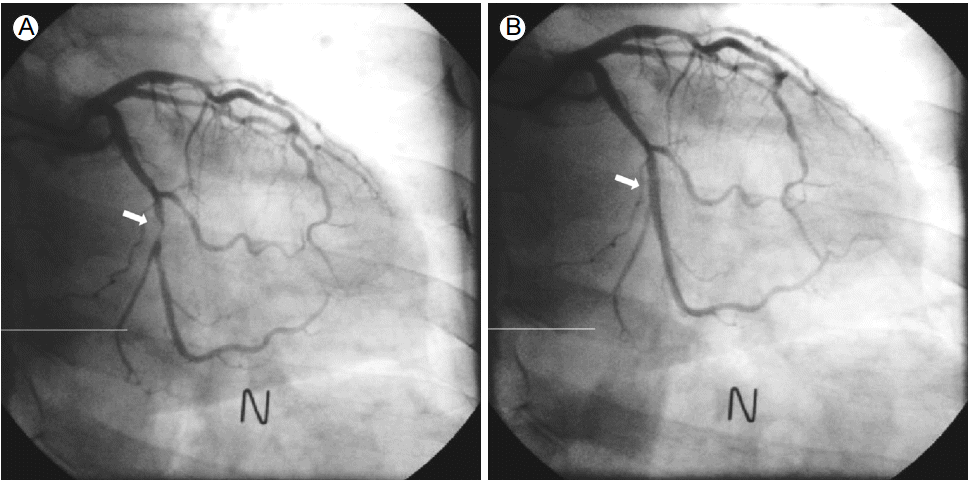

A 69-year-old male was hospitalized for coronary intervention after evaluation by computed tomography (CT) revealed critical stenosis of the distal left circumflex artery (LCX).The patient underwent coronary angiography via the left radial route with a 6 French (Fr) sheath (Terumo Corp., Tokyo, Japan) inserted using standard techniques. The left radial angiography showed a minor degree radial artery spasm (Fig. 1A). After injecting 200 μg of nitroglycerin via the radial artery, coronary angiography was successfully performed with 5 Fr JL4 and JR4 diagnostic catheters. The distal LCX lesion was similar to the lesion revealed by the coronary CT scan (Fig. 2A); therefore, PCI was deemed the best treatment option. During insertion of a 6 Fr extra back-up (EBU) guiding catheter (Medtronic, Dublin, Ireland) over a 0.035-inch standard guidewire, the catheter encountered resistance and the patient complained of pain in the left forearm. After removing the 6 Fr EBU guiding catheter, radial angiography was performed by injecting diluted contrast agent through the side port of the sheath. The contrast agent revealed perforation and extravasation of contrast agent into the surrounding tissue (Fig. 1B). A 5 Fr EBU was able to pass the perforated segment over the remaining 0.035-inch standard guidewire. PCI was performed successfully with balloon angioplasty and a 2.75 X 18-mm stent (Resolute integrity, Medtronic, Dublin, Ireland) (Fig. 2B). After removing the guiding catheter, radial angiography was performed via the sheath’s side port. The procedure showed that the perforation was sealed and that there was no contrast agent extravasation (Fig. 3).The patient was discharged after 48 hours without any local vascular complications, with a patent radial pulse, and no local hematoma.

Figure 2.

Successful percutaneous coronary intervention of the left circumflex artery (arrow) via the radial artery after perforation (A, B). N, nitroglycerin.